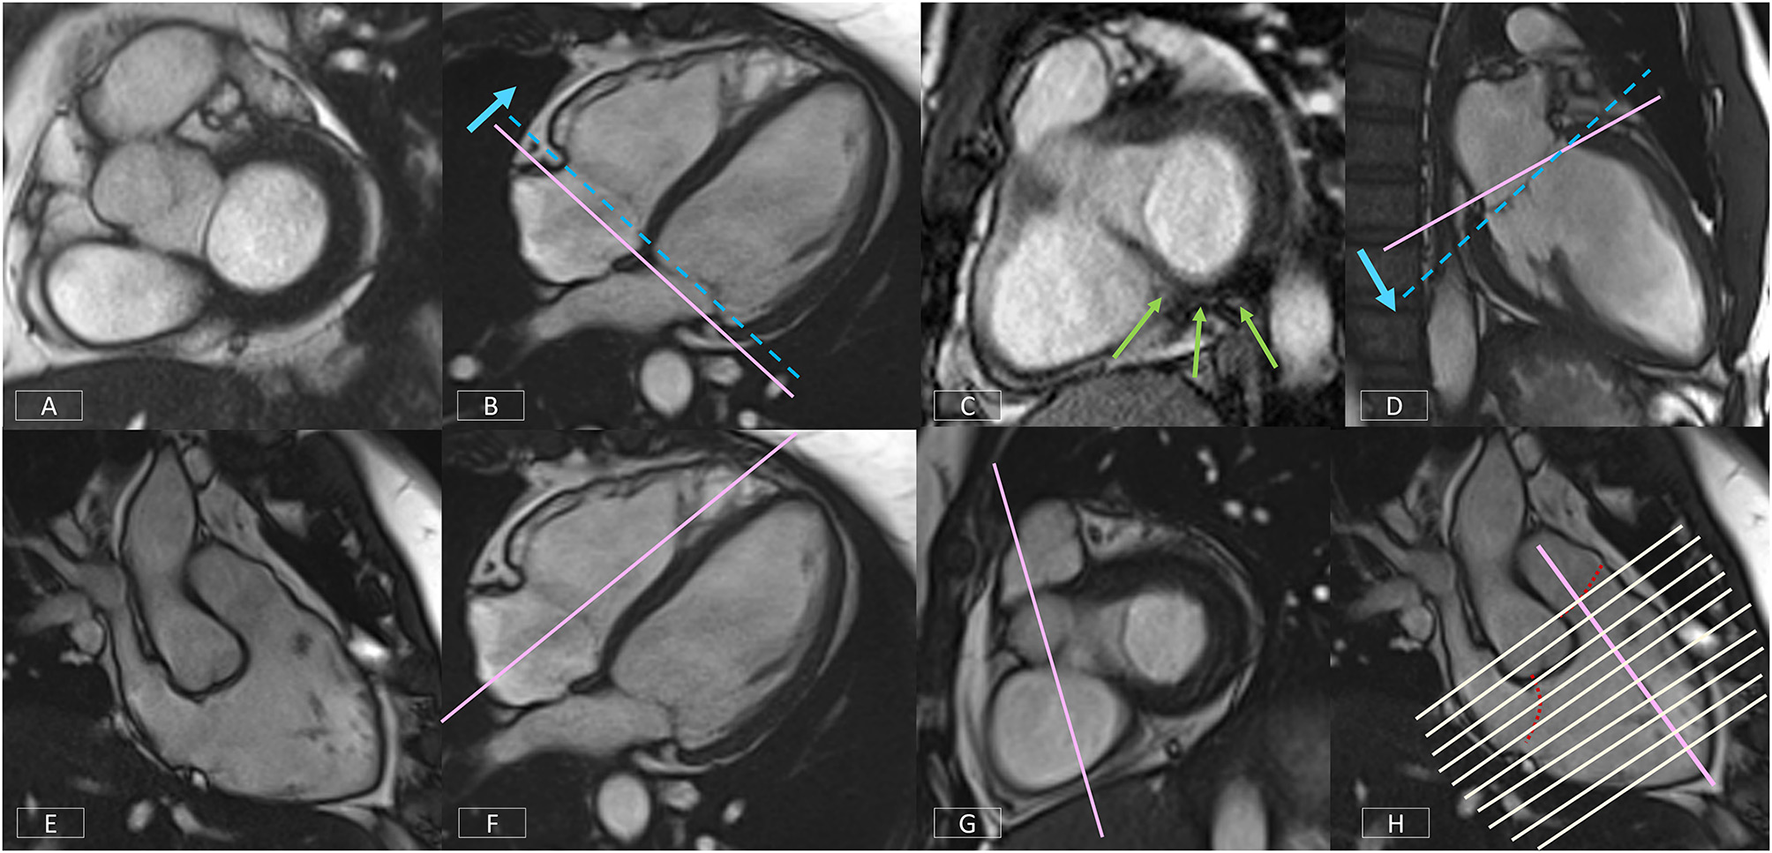

Figure 10

Top row: Positioning corrections for the LV SAX series include repositioning the slice more apically (B) if the basal diastolic phase slice includes atrium (A). If there is an inconsistent amount of myocardium around the blood pool (C), the slice angle is tilted on the LV VLA view (D). Bottom row: A well-positioned RV VLA (E) is achieved by positioning the slice on the 4-chamber view (F) through the RV apex and avoiding the septum, then tilting the slice plane up to the RVOT and pulmonary valve on the basal LV SAX slice (G). The RV SAX series can then be planned on this view to transect the tricuspid valve at an angle between 45° and 90° (H).

Right Ventricular Vertical Long Axis View

The non-geometric shape of the RV increases the complexity of positioning. A well-positioned RV VLA (Figure 10E) will enable visualization of the pulmonary and tricuspid valves, the RVOT and the RV apex in one plane. After positioning the slice on the 4-chamber view (Figure 10F) through the RV apex and avoiding the septum, the slice plane is tilted up to the RV OT and pulmonary valve using the basal LV SAX slice (Figure 10G).

Right Ventricular Short Axis

The modified RV short axis series (122) enables more accurate and reproducible planimetry of the ventricular borders making analysis less prone to operator error. A well-positioned RV VLA is key to ensuring correct positioning of the RV SAX.

Figure 10H shows the prescription of the RV SAX slices on the RV VLA. The slices should transect the tricuspid valve at an angle between 45° and 90° to ensure the slices are not prescribed too close to parallel to the valve.